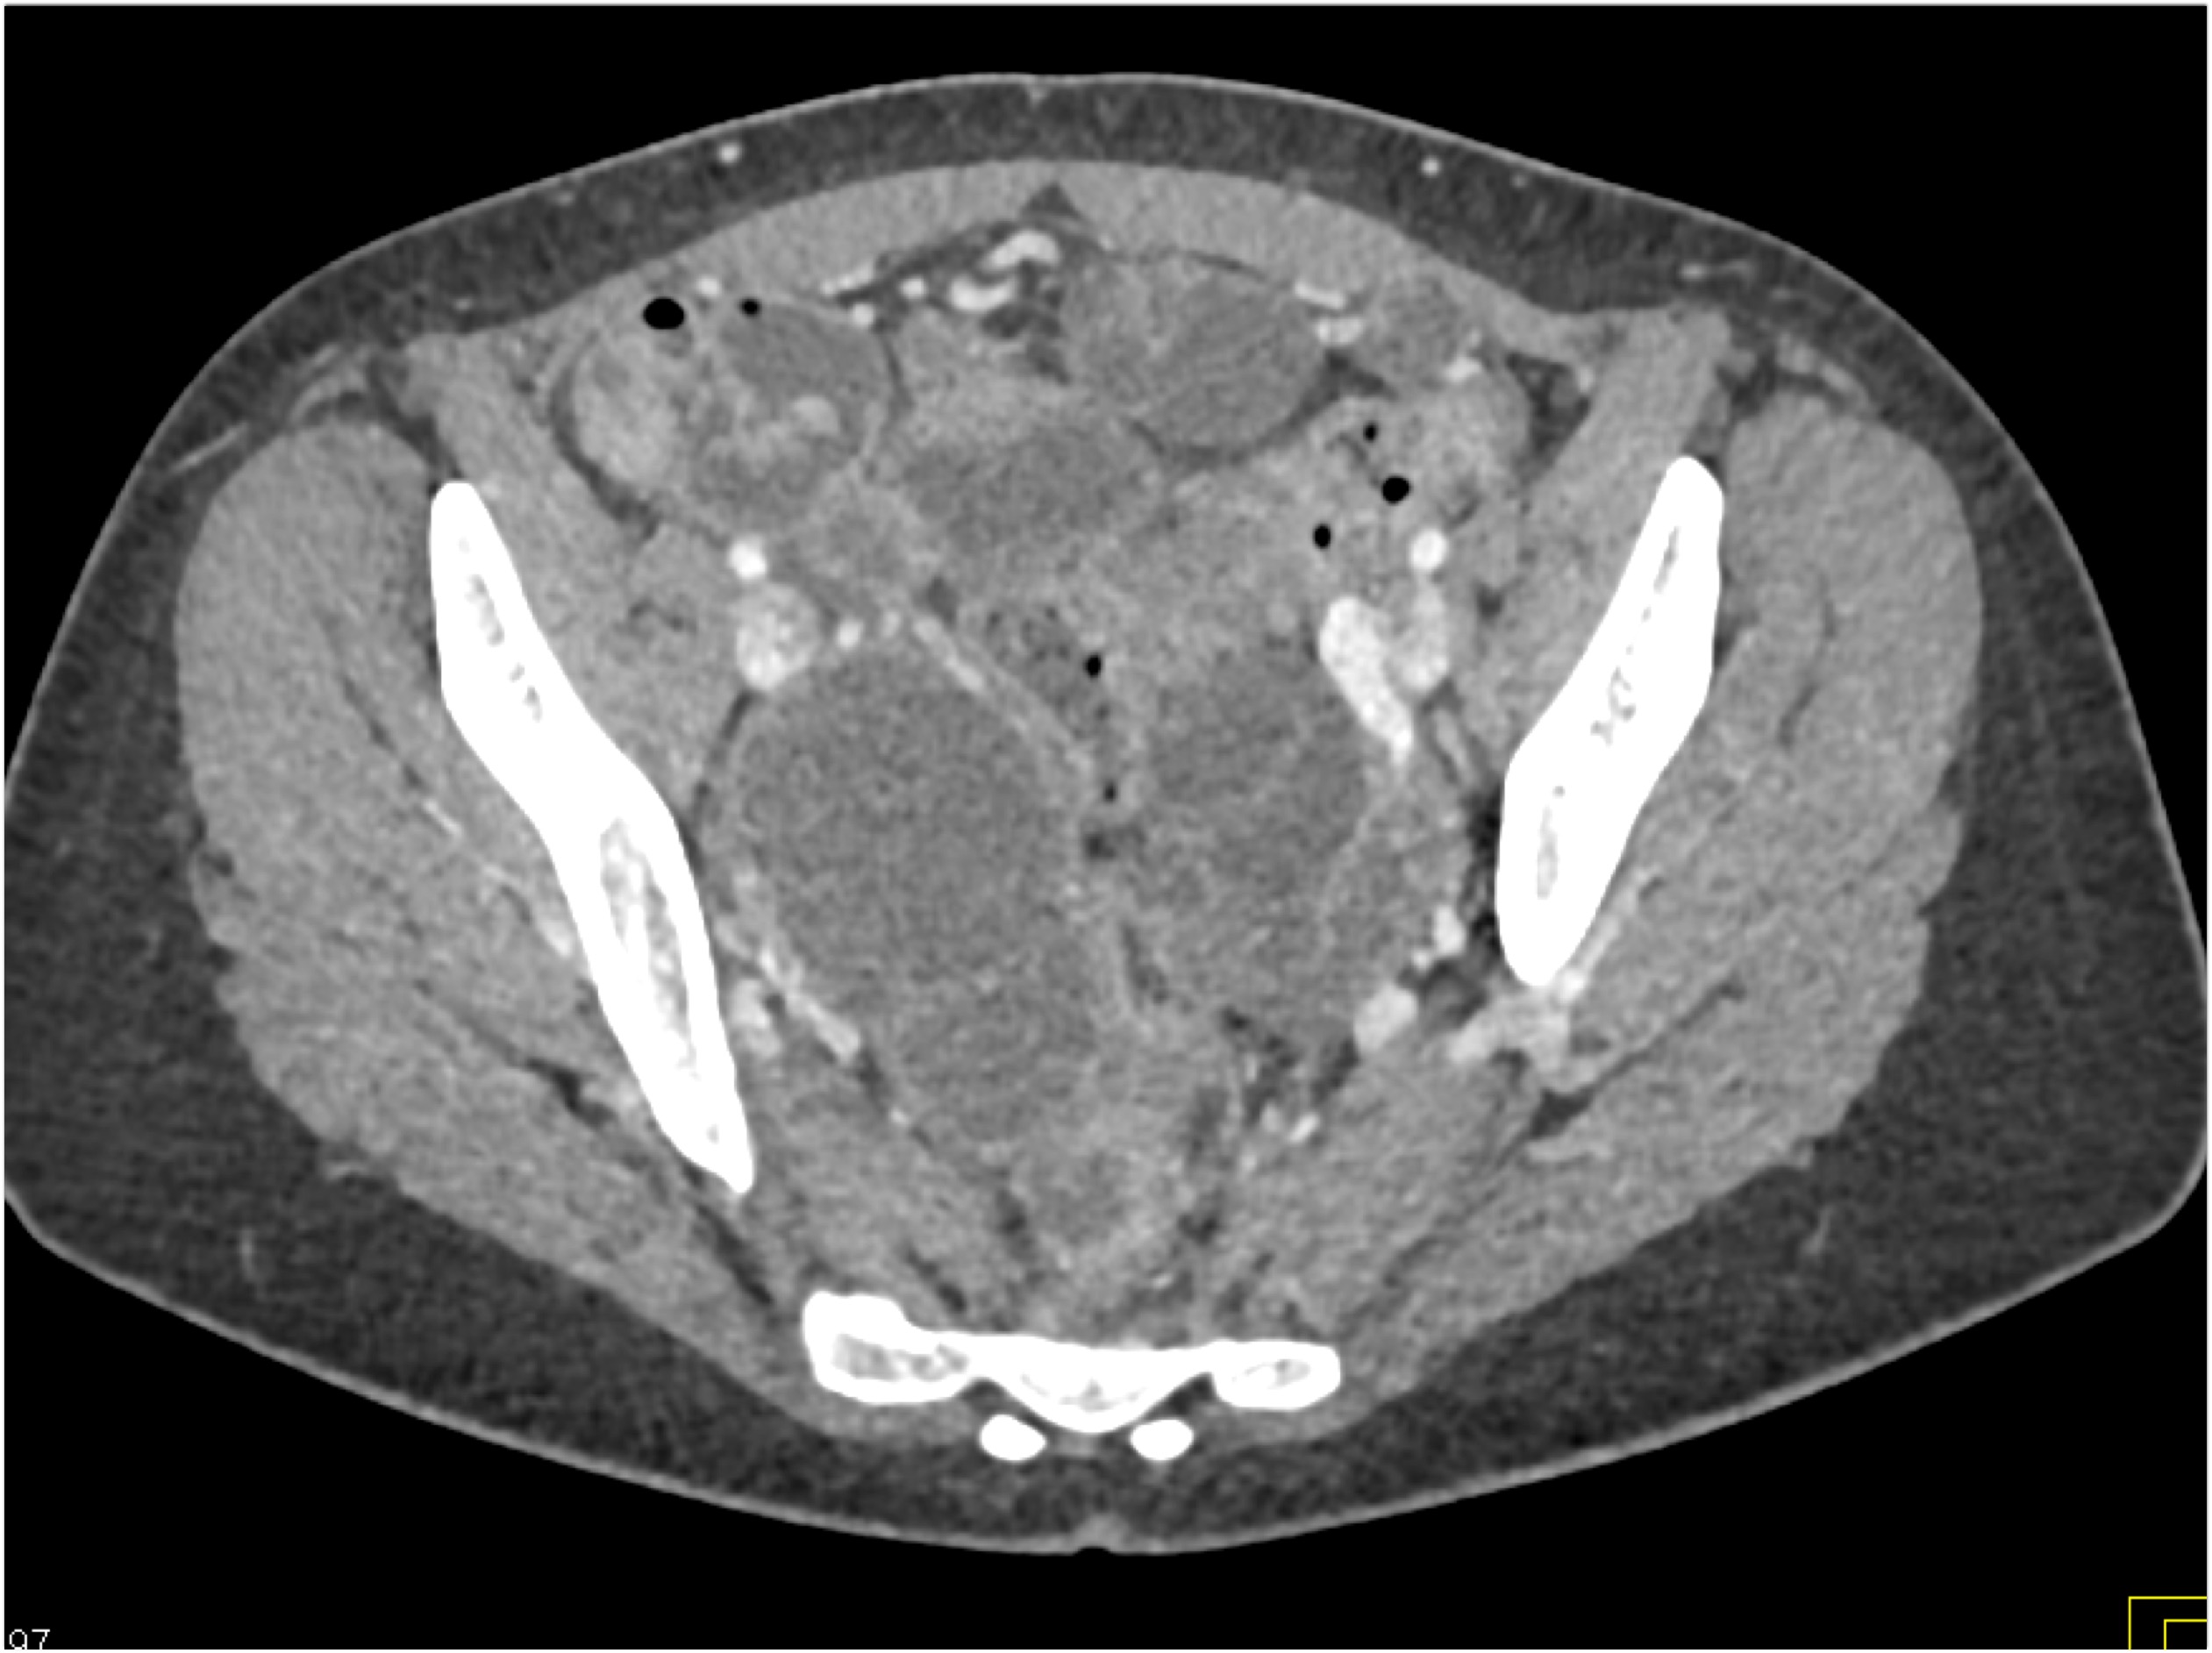

- Evaluate the CT images of each question carefully.

- Take time to make the call on the diagnosis for each individual question.